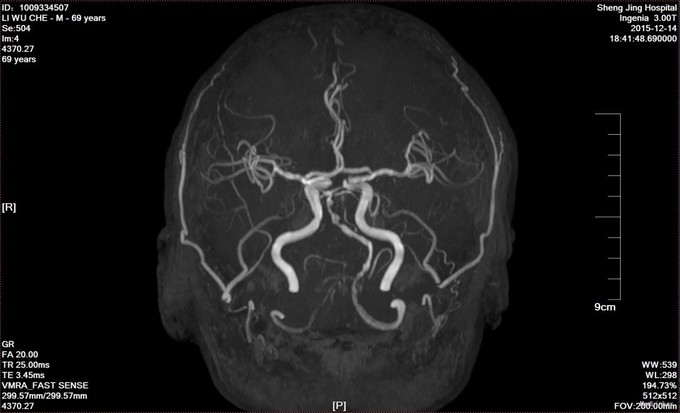

椎基底动脉供血不足 给予营养神经,改善循环,抗血小板,抗动脉硬化,抗氧化治疗,介入科会诊意见,该患者不适合手术治疗。

椎基底动脉供血不足是临床上常见疾病,但对于该患者,基地动脉狭窄明显,多次因头晕住院治疗,内科保守治疗效果有限,必定发展为急性脑梗塞,但介入对于后循环治疗尤其是基底动脉治疗风险非常大,对于患者的治疗有种束手无策的感觉,希望将来能够有更好的治疗办法。